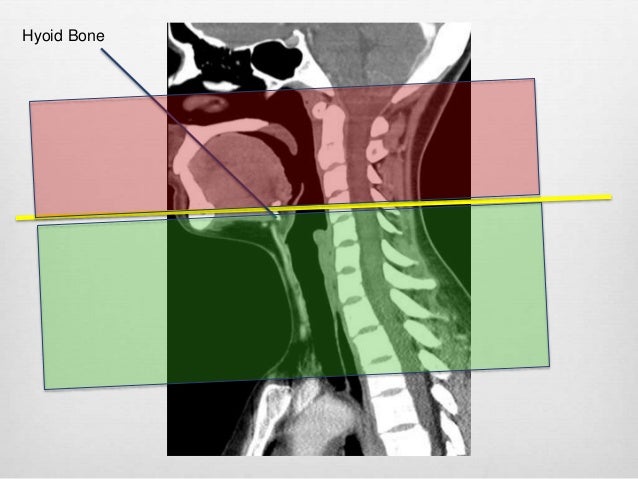

B11introbone

B11introbone www.slideshare.net